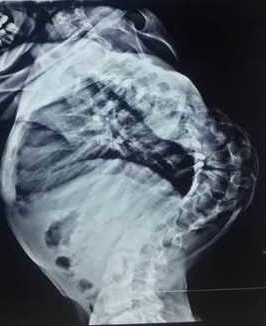

小婷婷今年13岁,十余年前无意间发现脊柱向侧后方弯曲,进行性加重,而且背部出现一个很大的罗锅畸形,曾去国内多家知名医院求医,终因风险及难度极大,而放弃治疗。后来打听到西安交大二院贺西京教授在治疗脊柱的疑难病、复杂病中有丰富的经验,慕名而来。小婷婷住院后,得到了贺西京教授、李浩鹏主任及治疗小组医护人员的关爱和重视。因患儿脊柱畸形严重,脊柱向外成角超过160度,而且胸廓畸形,心肺功能严重受影响,手术难度与风险极大,不宜直接做手术矫形。经专家讨论,先采用头颅及双下肢骨牵引术,将弯曲礓硬的脊体牵长、拉软。在持续牵引2周后,胸廓畸形、椎旁肌肉僵硬等情况得到较大改善。尽管这种牵引对患儿很痛苦,但得到了患儿及家长的理解和配合,为手术的顺利进行做好了准备。